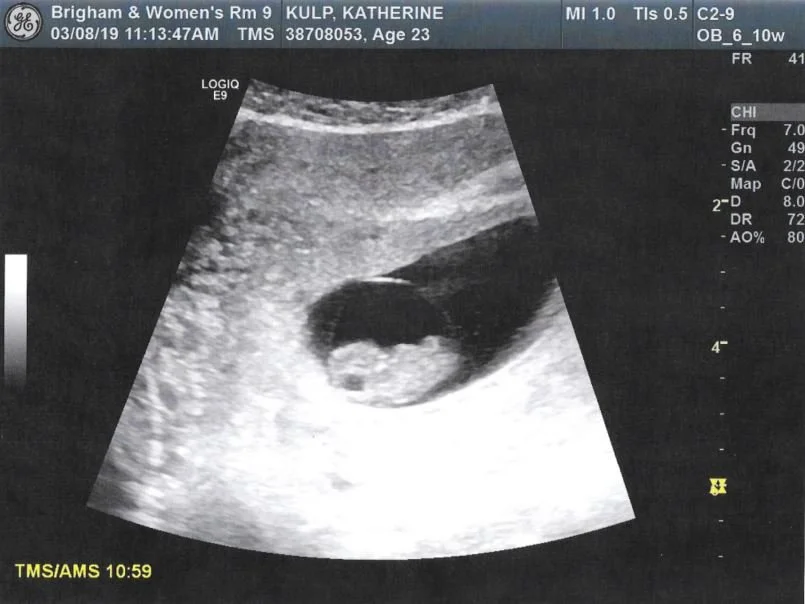

Before I became a mother, the story of Mary and her baby Jesus was familiar yet foreign to me. What did it mean to carry a child that was both yours and not yours? To feel the weight of new life growing inside you, knowing that that life was a precious gift from God Himself?